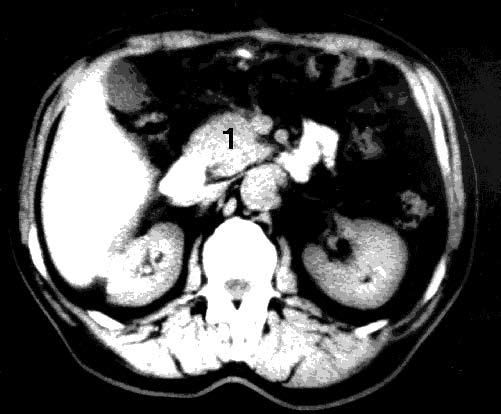

Рис. 99. Компьютерная томография. Рак головки ПЖ. На снимке видна гиподенсная бугристая опухоль головки ПЖ 4x5 см (1)